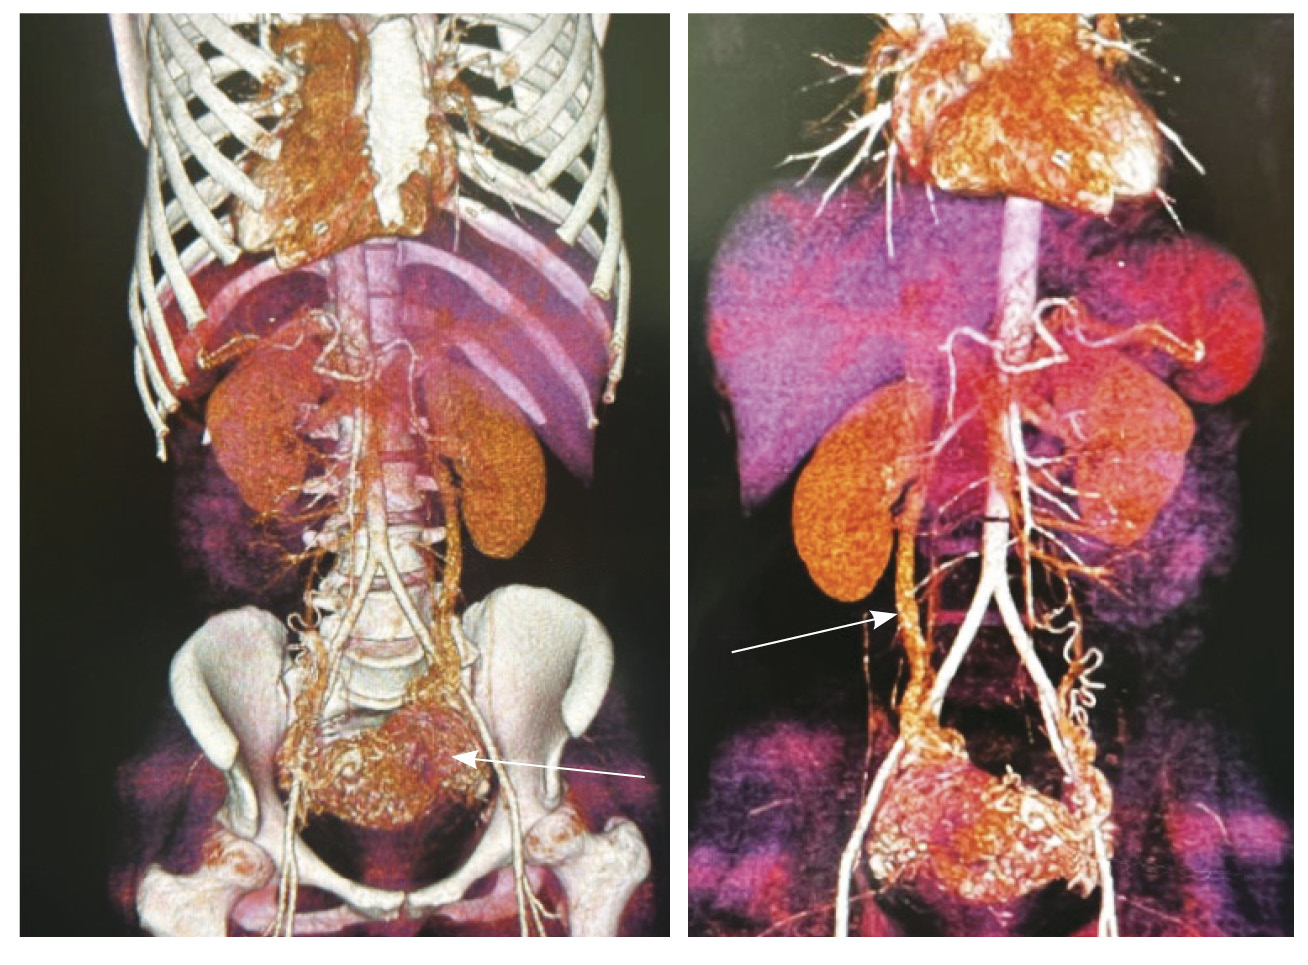

Для детализации сосудистого компонента артериовенозной мальформации, в том числе с целью планирования дальнейшей лечебной тактики, пациентке выполнено КТ-исследование (рис. 3). Обнаружено: тело матки увеличено, определяется образование в полости матки неясного генеза. В стенках матки сосудистая артериальная сеть с ранним сбросом контрастного вещества во внутреннюю подвздошную вену с двух сторон (диаметром 0,7 см справа, 0,8 см – слева), правую яичниковую вену (диаметром до 1,2 см), левую яичниковую вену (диаметром до 0,6 см).

Рис. 3. Компьютерная томограмма органов таза с контрастированием. Тело матки увеличено, в стенках матки сосудистая артериальная сеть (стрелки) с ранним сбросом контрастного вещества во внутреннюю подвздошную вену с двух сторон, правую и левую яичниковые вены (стрелка)